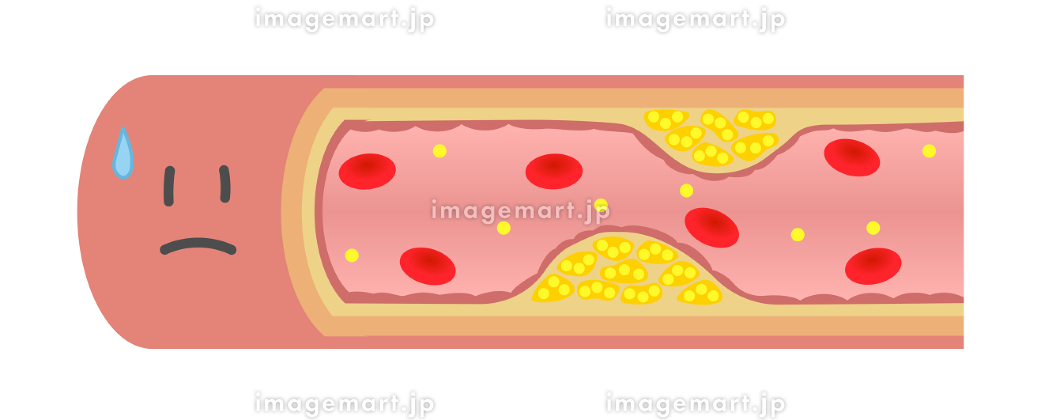

血栓症」のイラスト素材・ベクター画像 - イメージマートimagemart。

血栓症」のイラスト素材・ベクター画像 - イメージマートimagemart。

正常な血管と血栓ができた血管 イラスト素材5358451- フォトライブラリ。

血栓症」のイラスト素材・ベクター画像 - イメージマートimagemart。

血栓症」のイラスト素材・ベクター画像 - イメージマートimagemart。

動脈硬化、血栓形成。ベクトル医療イラスト。内部の臓器、血栓症、血管内皮のイラスト素材・ベクター Image 61855962。